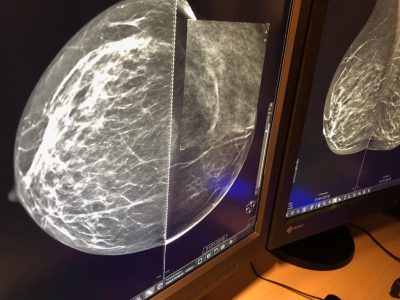

Mammografia 3 D, scoprire i tumori “invisibili”: ecco come funziona e quando è necessaria la tomosintesi